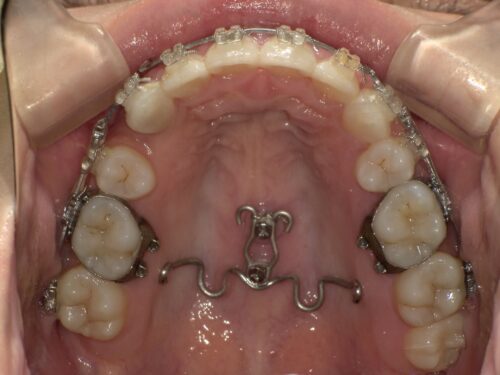

治療中・上顎の写真

抜いたスペースが少なくなってきているのがわかると思います。

この段階では、上の歯は抜歯済みで後方に動かしながら、下顎にも装置が装着されました。上下同時に歯並びを整えていきます。